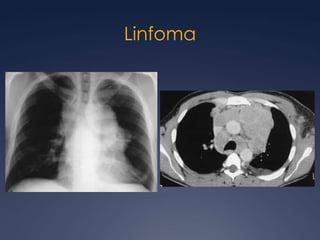

LinfomaNeoplasia mediastinal más frecuente en adultosLH: 85% tórax90% adenomegalias mediastinales.LNH: 50% mediastino (linfoma linfoblástico y linfoma de células B grandes)Brant and Helms:  389-416

Linfoma de HodgkinCLÁSICAEsclerosis nodular  Celularidad mixtaRico en linfocitosDepleción linfocitariaNO CLÁSICANodular de predominio linfociticoBrant and Helms:  389-416

Hodgkin, nodular esclerosante

Mediastino Anterior 90%

Confinado solo a M.Anterior, únicamente 40%

Masas ganglionares

A veces hipodensas por necrosis

Calcificadas después de tratamientoLinfoma de Hodgkin

LinfomaRadioGraphics 2007; 27:657– 671

Linfoma

Generalmente isodensos al músculo en CTNecrosis y calcio en postquimioterapiaHiperintensos T2 RMPET/CT tamaño normal pero actividad metabólicaLinfoma No Hodgkin

Linfoma No Hodgkin